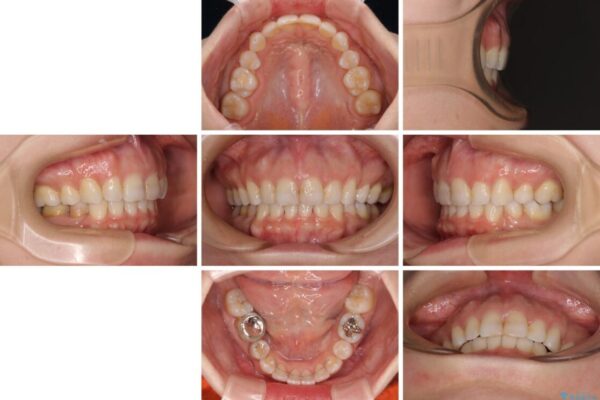

治療途中

• 【モニター】出っ歯と咬み合わせを改善 ワイヤー装置の抜歯矯正 治療途中画像

左下の大臼歯2本が顕著に舌側に傾斜しているため、まずは奥歯の咬み合わせを改善をし、その後上下左右の第1小臼歯4本を抜歯することで口元を引っ込めながら整えることとしました。

奥歯の咬み合わせ改善には1年ほどの期間と処置中の噛みにくさを強いることとなりましたが、抜歯後はスムーズに治療を完了させることができました。